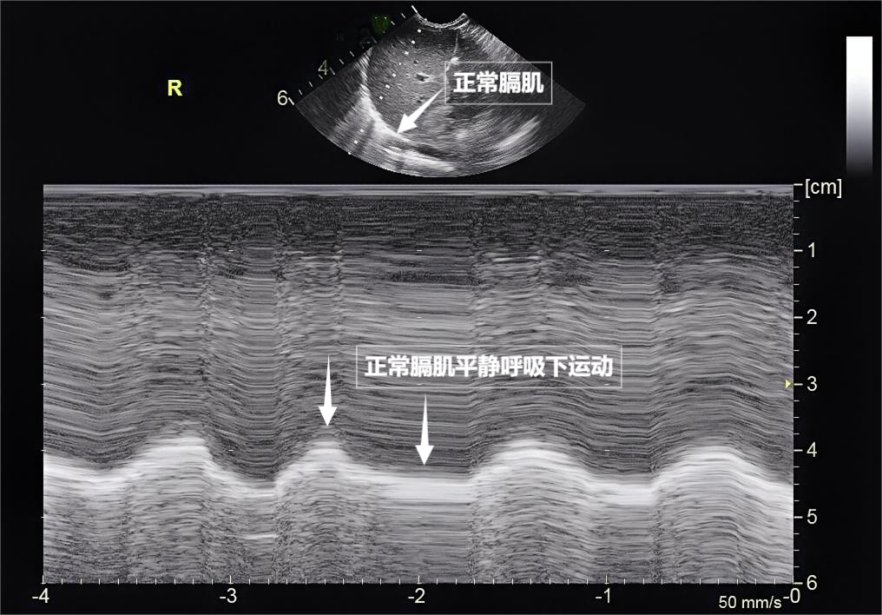

呼吸看似简单,实则是多组肌肉精密配合的“团体操”。肺部超声不仅能观察肺的形态,更能通过实时动态影像,“捕捉”这些呼吸肌的活动状态,为评估呼吸功能提供独特视角。膈肌是呼吸肌的“总指挥”,位于胸腔与腹腔之间。平静呼吸时,膈肌收缩下沉,胸腔容积扩大,空气自然吸入;舒张时,膈肌回升,肺部弹性回缩完成呼气。超声下可见膈肌呈光滑弧形,随呼吸规律上下移动(见下图

)。肋间外肌则是“肋间隙的升降机”,收缩时上提肋骨,扩大胸腔前后径,辅助吸气。这对“黄金搭档”承担了日常呼吸70%以上的工作量,是维持呼吸的“主力军”。

图为正常膈肌超声表现